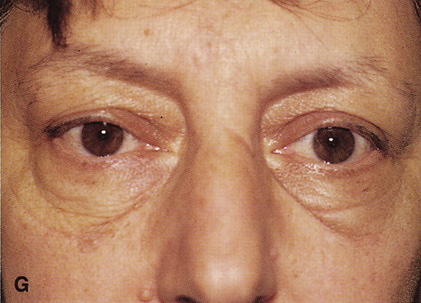

Fig. 6. Lateral orbitotomy through upper eyelid skin crease A. Photo demonstrating right globe ptosis present for more than 2 years. B. Axial CT scan showing a well outlined oval lesion in the lacrimal gland

fossa. C. Coronal CT showing lesion pushing globe inferiorly. D. Skin crease excision marked for lateral orbitotomy. E. Lateral orbital rim exposed. Bone cuts made above frontozygomatic suture

and at zygomatic arch. F. Lateral wall removed. Subperiosteal space exposed. Hard tumor could be

palpated in area of lacrimal gland. G. Benign mixed tumor of lacrimal gland removed. H. Bone sutured into place. I. Skin crease closed. |